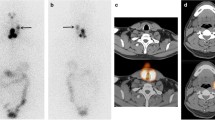

A 53-year-old female patient presented to the department of nuclear medicine outpatient clinic of Seoul National University Bundang Hospital in January 2020 due to an exophytic thyroid nodule. She underwent thyroid ultrasonography that revealed a large nodule (3.44 × 2.14 × 4.84 cm) in the left thyroid lobe. A benign follicular nodule was confirmed through fine needle aspiration cytology. No specific abnormality was observed on the right lobe (Fig. 1a, b). On planar scan and SPECT/CT (NMCT670, GE) using Tc-99m pertechnetate (5 mCi), a hot nodule was observed in the left thyroid lobe, while the right thyroid lobe was not visualized (Fig. 1c, d). The percentage of thyroid uptake of the hot nodule found on the left lobe increased to 4.70%, whereas that of the right lobe decreased to 0.04% (normal range 0.78 ± 0.5%) (Lee et al. 2016). Details of the Tc-99m pertechnetate scan and SPECT/CT procedure are provided in the Additional file 1. The thyroid hormone profile assessed via radioimmunoassay was consistent with T3 thyrotoxicosis (Additional file 1: Table S1). The patient provided an informed consent to undergo the therapeutic approach. The study was approved by the institutional ethical review board.

An autonomously functioning thyroid nodule. The neck ultrasound does not show abnormal findings in the right lobe (a), while a large thyroid nodule (3.44 × 2.14 × 4.84 cm) is observed in the left thyroid lobe (b). Tc-99m pertechnetate scan reveals a hot nodule in the left lobe, while the right lobe is suppressed, as demonstrated on the planar scan (dotted line) (c) and SPECT/CT (small arrows) (d). SPECT single-photon emission computed tomography

The AFTN in the left lobe had the highest uptake at 4-h I-123 SPECT/CT (Fig. 2a). The quantitative SPECT/CT (Q.Volumetrix MI, GE) was used to measure the I-123 concentrations (12.99 µCi/mL, 24.82 µCi/mL, and 12.26 µCi/mL) and the I-123 uptake fractions (0.10, 0.20, and 0.10) at 1-h, 4-h, and 24-h SPECT/CT, respectively (blue in Fig. 2b). The contralateral right lobe showed faint uptake on all the SPECT/CT studies (Fig. 2a); the I-123 concentrations were 0.24 µCi/mL, 0.28 µCi/mL, and 0.11 µCi/mL, while the I-123 uptake fractions were 0.0005, 0.0006, and 0.0002 at 1-h, 4-h, and 24-h SPECT/CT, respectively (blue in Fig. 2c).

Quantitative I-123 SPECT/CT. Coronal (upper row) and transaxial (bottom row) SPECT/CT images at 1 h, 4 h, and 24 h post I-123 administration (a). The measured concentration of I-123 (blue) and expected concentration of I-131 (green) for the hot nodule in the left lobe (b) and the contralateral right thyroid lobe (c). RAI radioactive iodine, SPECT single-photon emission computed tomography

Assuming that 5 mCi of I-131 was administered, the expected I-131 concentrations of the AFTN were calculated as 13.56 µCi/mL, 29.78 µCi/mL, and 38.59 µCi/mL, while the uptake fractions were 0.11, 0.14, and 0.31 at 1 h, 4 h, and 24 h, respectively (green in Fig. 2b), thus suggesting that I-131 was not rapidly metabolized (Silberstein et al. 2012). On the contrary, the expected I-131 concentrations in the normal right thyroid lobe were 0.25 µCi/mL, 0.34 µCi/mL, and 0.34 µCi/mL, while the uptake fractions were 0.0005, 0.0007, and 0.0007 at 1 h, 4 h, and 24 h, respectively (green in Fig. 2c).